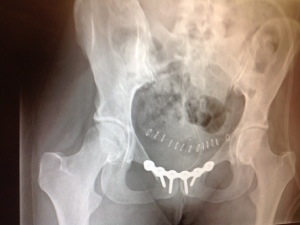

After surgery — you can see my 13 staples in this image, along with the plate and screws. The staples are gone. The rest of it stays.